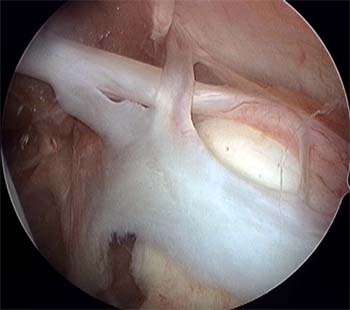

La reparación artroscópica de la lesión SLAP la realizamos en posición de silla de playa con el brazo en tracción manual por un asistente, con 30-40 de Abducción y 20 grados de flexión anterior. Con bloqueo anestésico interescalenico del plexo braquial, más sedación con infusión de propofol y con bomba de infusión continua a 30-35 mmHg. Por un portal posterior estándar para visualización, se realiza una evaluación de la unidad funcional bíceps labrum con un gancho palpador en busca de inestabilidad de la inserción del labrum superior, signo de despegamiento o peel-back, signo de drive through o paso a través. Una vez que se realiza el diagnóstico de lesión SLAP y se decide realizar la reconstrucción artroscópica, se realizan los portales accesorios antero inferior justo por encima del borde superior del subescapular y portal antero supero lateral justo por encima del tendón del bíceps, entrando a nivel del borde antero lateral del acromion. Ambos portales se realizan de afuera adentro, la localización correcta se busca mediante una aguja espinal y se realiza la colocación de cánulas de 7,25 mm con sistema de guías de dilatación progresiva (Arthrex inc. Naples Florida). La cánula antero inferior se la utiliza para manejo de sutura e instrumental y la cánula antero supero lateral para la colocación de los implantes y pasaje de sutura e instrumental. Por la cánula antero inferior se realiza el desbridamiento y cruentado de la lesión utilizando legras, raspas artroscópicas y shaver motorizado; para la preparación del lecho óseo por debajo del labrum desinsertado para mejor aporte biológico. La fijación de la lesión se realiza con arpones de titanio Fastak de 2,8 mm (Arthrex inc. Naples Florida) o preferiblemente con arpones bioabsorvibles BioSuture-Tak de 3 mm (Arthrex inc. Naples Florida). La colocación de los implantes se realiza de posterior a anterior. El primer arpón se coloca con guía de colocación del implante por la cánula antero supero lateral por detrás de la inserción del bíceps; si la lesión SLAP es muy posterior o la anatomía del portal antero supero lateral, no permite llegar con ángulo correcto de colocación del implante al cuadrante posterosuperior de la glena; se realiza la colocación del implante a través del portal de Wilmington directamente con la guía de colocación del implante con técnica transtendón en la unión músculo tendinosa, sin la colocación de cánulas artroscópicas para no dañar el manguito rotador. Luego de la colocación del implante se retira la sutura que se utilizara como poste por el portal antero inferior, por el portal antero supero lateral se realiza el pasaje de sutura con técnica de suture lazo; luego se realiza el anudado artroscópico desde el portal antero supero lateral. Según el tipo de lesión SLAP se realiza la colocación de 1 arpón por detrás y otro por delante del tendón del bíceps o 2 arpones por detrás de la inserción del bíceps. Para constatar la estabilidad de la reconstrucción, debemos corroborar la corrección del signo de despegamiento o peel-back y del signo de paso a través o drive through (Figura 5) (Ver video en pagina web).

Figura 5: A: Jugador de Rugby 20 años con SLAP tipo II combinado. B: Combinación de punto vertical y horizontal de 2 arpones por detrás de la inserción del bíceps. C: Resultado Final 2 arpones por detrás del bíceps y 1 arpón por delante del bíceps.